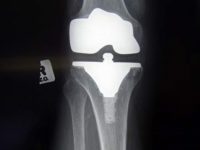

Os alimentos que podem danificar nossas articulações

Ao executar e praticar esportes é muito importante ter em mente que as articulações devem estar em perfeito estado. Você precisa ter uma musculatura para conseguir isso, mas o esporte não só é suficiente, uma vez que a nutrição adequada nos ajudará a alcançar fortes articulações, mas também alimentos podem fazer muito dano para as […]